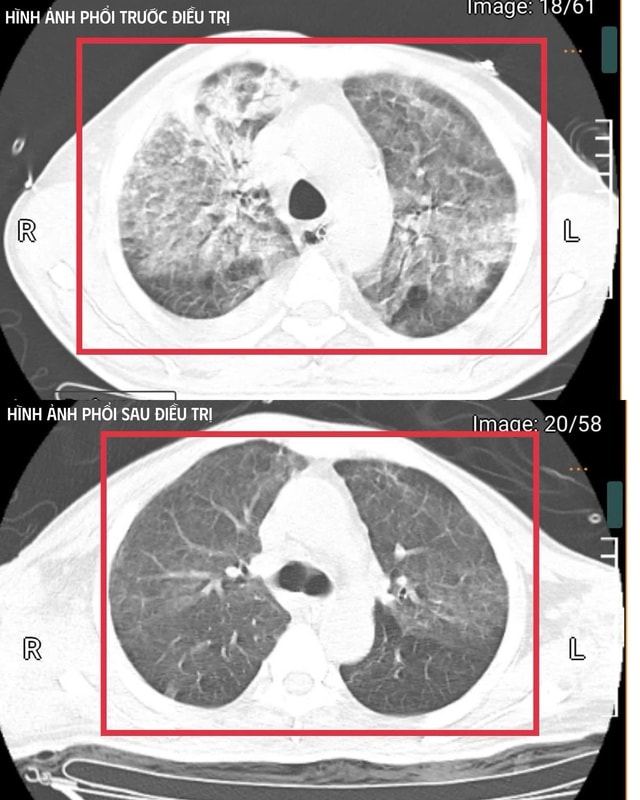

Sau khoảng ba ngày hồi sức tích cực, bệnh nhân bắt đầu cắt sốt, các chỉ số viêm và nhu cầu thuốc vận mạch giảm, chức năng gan thận cải thiện, tri giác hồi phục.

Bệnh nhân được cai máy thở (qua mở khí quản), tập hô hấp tự nhiên và phục hồi vận động. Sau ba tuần điều trị, bệnh nhân đã hồi phục hoàn toàn: tỉnh táo, tự thở khí phòng, huyết áp ổn định, cơ lực chi trên đạt 5/5, chi dưới 4/5. Bệnh nhân được xuất viện và tiếp tục theo dõi ngoại trú.